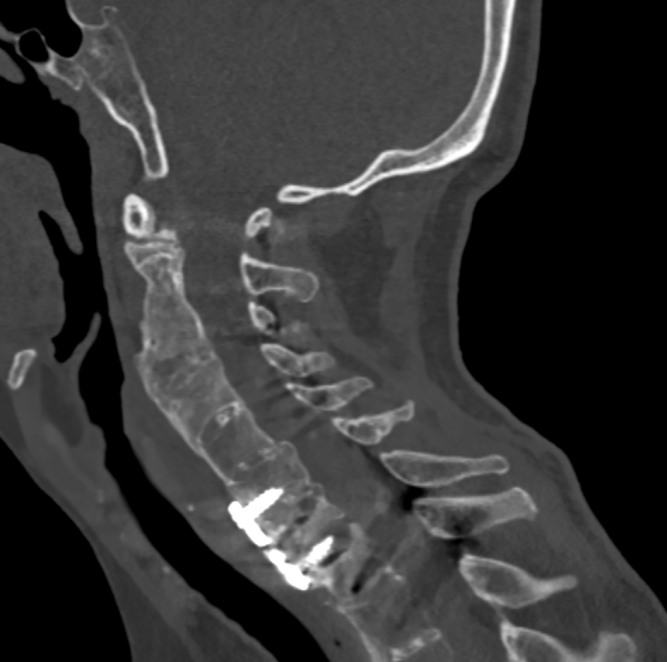

金先生伤后第7天,姜主任医师团队在麻醉手术科的密切配合下成功为他实施手术。姜主任凭借多年徒手置钉的过硬技术经验,2小时不到便完成了手术,术中出血仅100ml。术后CT显示齿状突完美复位,螺钉“不偏不倚”的位置恰到好处。术后,金先生在骨科护士长张霞芬护理团队的精心护理下,15天后伤口拆线康复出院。